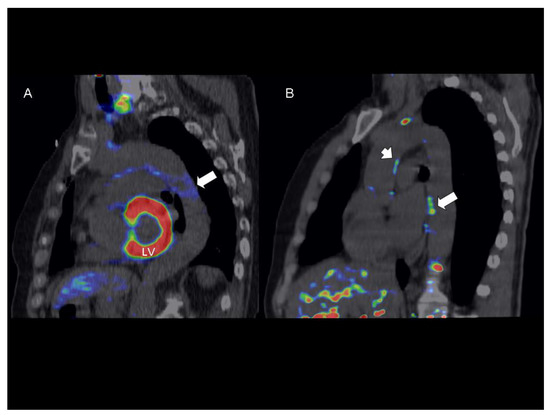

Table 2 shows that there were no differences in terms of OCT-assessed features of coronary plaque vulnerability between the two study groups. Overall, patients with low levels of cystatin C were more likely to have a higher FDG uptake in the aortic wall and CAC score. When modelled as continuous variable, cystatin C levels showed a strong trend towards an inverse relationship with the number of active slices in DA (rho = −0.35, p = 0.06). Yet, after multivariable analysis, levels of cystatin C were independently associated with FGD uptake in DA as measured by either averaged max TBR or number of active slices (Table 3). Figure 2A depicts a 18F-FDG-PET/CT scan from a patient in the high cystatin group showing no significant FDG uptake in the DA (max TBR = 1.3), whilst a further 18F-FDG-PET/CT scan from a patient in the low cystatin C group shows an active (max TBR = 2.0) focus of FDG uptake in the DA wall (Figure 2B). There were no active slices in the AA, in both cases. Finally, no trend was found for the association of cystatin C and CAC score. Figure 3 shows that areas of FDG uptake in the aortic wall are not related to the presence of calcification.

Figure 3.

Representative 18F-FDG-PET/CT image of thoracic aorta showing a big focal calcification (arrowhead) not related to significant 18F-FDG uptake (TBRmax = 1.3). In the descending aorta, an active focal 18F-FDG uptake (arrow) is also shown (TBRmax = 1.8). Abbreviations: 18F-FDG-PET/CT = 18F-fluorodeoxyglucose-positron emission tomography/computed tomography; TBR = target to background ratio.